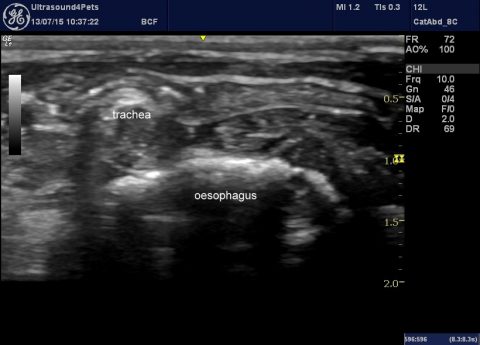

Recently I’ve seen two three-month-old dogs with multiple (numerous) small portosystemic shunts in the absence of inflammatory liver disease. The patient whose images are presented below was examined on account of acute encephalopathy with bile acids >130 umol/l and ALT > 600 (ref <100). The same in video: This flow courses via colic veins to enter … Continue reading